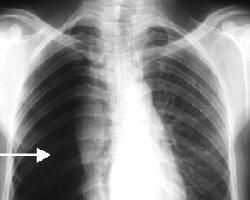

主要根據X線檢查確診。

胸部X線檢查可顯示不同程度的肺萎陷和胸膜腔積氣,有時尚伴有少量積液。

根據患者的病史、症狀體徵,以及胸部X線結果即可明確診斷。